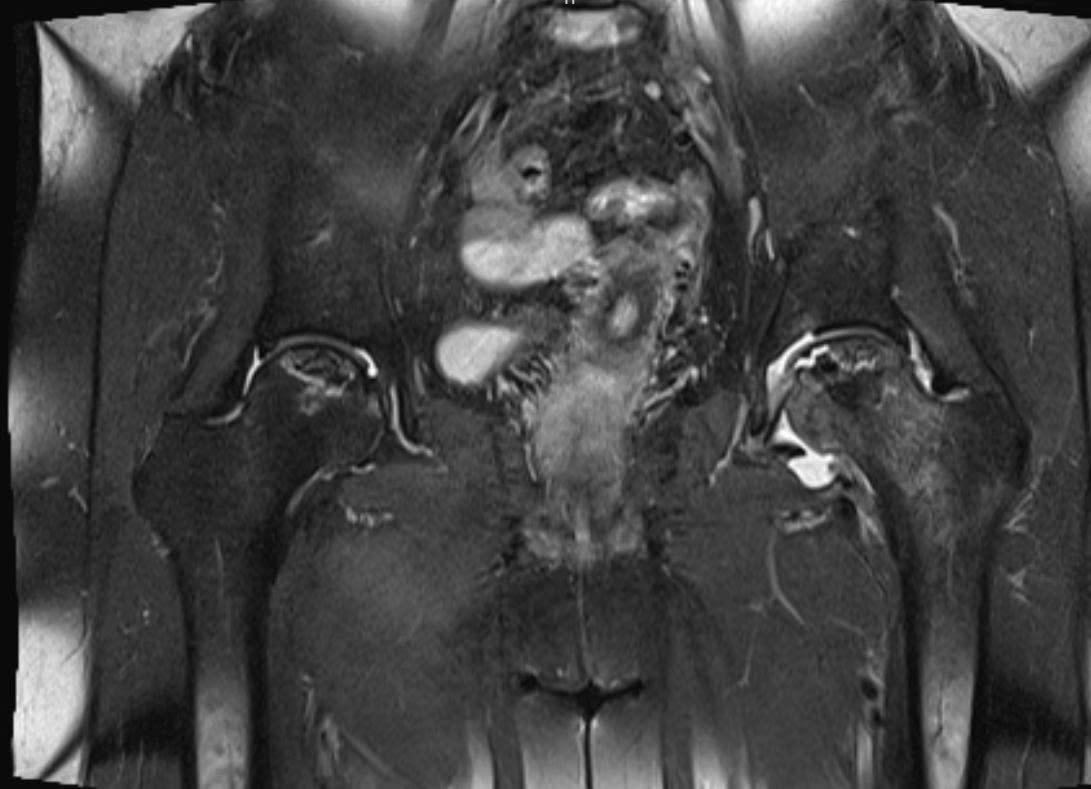

Thăm khám chuyên sâu và chụp MRI - bước ngoặt trong điều trị

Tại AIH, Bác sĩ CKII Nguyễn Viết Thịnh - Phó Khoa Ngoại Tổng quát tại Bệnh viện Quốc tế Mỹ (AIH) thăm khám lâm sàng kỹ lưỡng và xem xét lại toàn bộ phim X-quang trước đó. Dù hình ảnh X-quang không cho thấy tổn thương rõ ràng, dựa trên triệu chứng lâm sàng và diễn tiến bệnh, bác sĩ nghi bệnh nhân mắc hoại tử vô mạch chỏm xương đùi. Đây là một bệnh lý thường khó phát hiện ở giai đoạn sớm nếu chỉ dựa vào X-quang thông thường.

Sau đó, bệnh nhân được chỉ định chụp MRI khớp háng. Kết quả cho thấy tình trạng hoại tử chỏm xương đùi xuất hiện ở cả hai bên, với mức độ tổn thương rõ rệt, xác định bệnh đã tiến triển đến giai đoạn nặng, không còn phù hợp với các phương pháp điều trị bảo tồn, từ đó làm cơ sở cho quyết định can thiệp phẫu thuật thay khớp háng.

BS.CKII Nguyễn Viết Thịnh cho biết: “Hoại tử vô mạch chỏm xương đùi thường tiến triển âm thầm và dễ bỏ sót ở giai đoạn đầu nếu chỉ dựa vào X-quang hoặc thăm khám lâm sàng chưa đầy đủ. Nếu bệnh nhân được chẩn đoán sớm hơn bằng MRI, nhiều trường hợp có thể áp dụng các phương pháp điều trị bảo tồn hoặc can thiệp ít xâm lấn, giúp trì hoãn hoặc tránh phải thay khớp háng.”